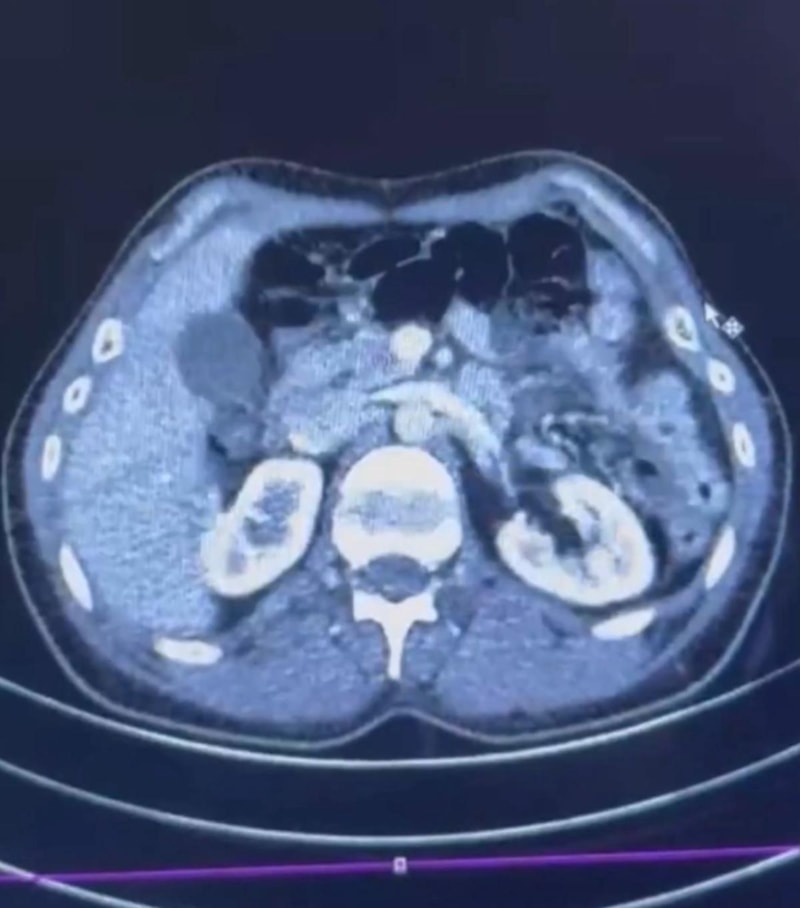

Röntgeni ve ultrason çekilen şüphelilerin midesinde, yaklaşık 50 kapsülde 554 gram uyuşturucu olduğu tespit edildi.